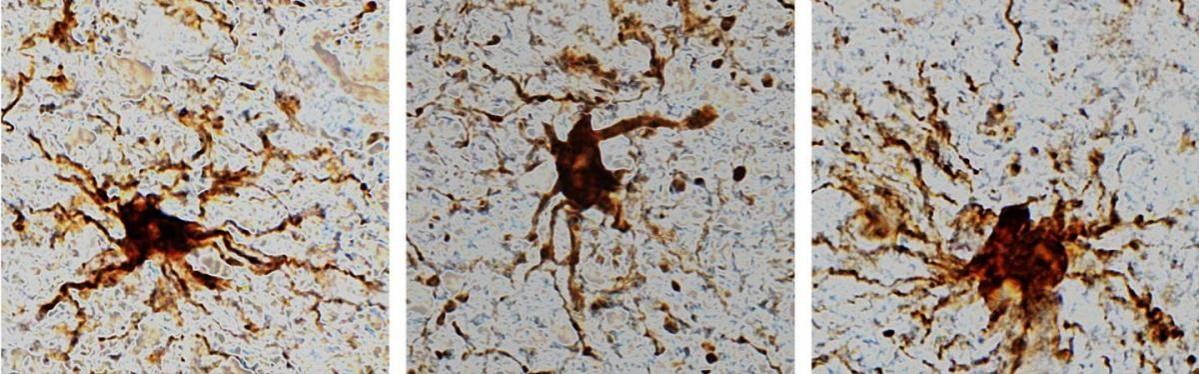

These 'zombie genes' -- those that increased expression after the post-mortem interval -- were specific to one type of cell: inflammatory cells called glial cells. The researchers observed that glial cells grow and sprout long arm-like appendages for many hours after death.

"That glial cells enlarge after death isn't too surprising given that they are inflammatory and their job is to clean things up after brain injuries like oxygen deprivation or stroke," said Dr. Jeffrey Loeb, the John S. Garvin Professor and head of neurology and rehabilitation at the UIC College of Medicine and corresponding author on the paper.

A third group of genes -- the 'zombie genes' -- increased their activity at the same time the neuronal genes were ramping down. The pattern of post-mortem changes peaked at about 12 hours.